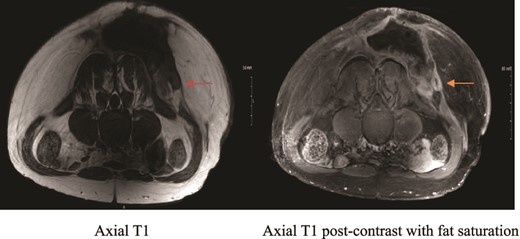

Private hospital MRI. Axial T1 MRI (left) shows left rounded low T2 signal intensity lesion (orange arrow), which shows hyperenhancement (green arrow) on axial T1 fat saturated postcontrast images (right).